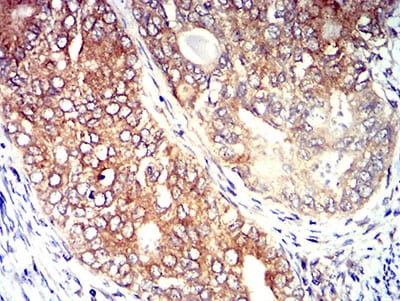

分类: 科研抗体货号: 31308别名: P2Y8应用: IHC,IF,FCM反应种属: Human

分类: 科研抗体货号: 31307别名: P2Y8应用: IHC,IF,FCM反应种属: Human